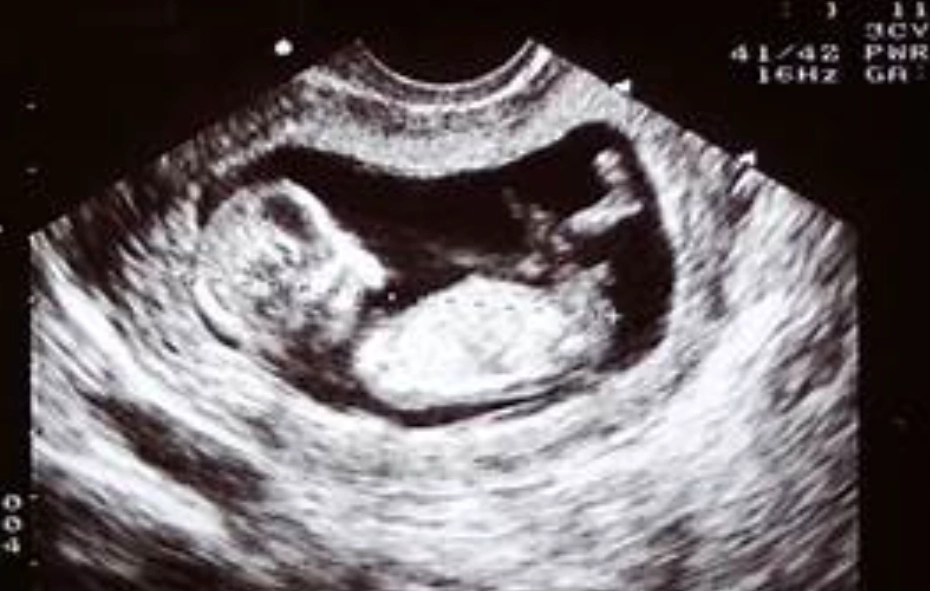

- Movement: Oh, they're moving! Kicking, stretching, even making little fist clenches. You won't feel it for several more weeks, but on an ultrasound, it's a beautiful, wiggly sight.

It's truly astonishing how much is accomplished in this first trimester. The Mayo Clinic provides excellent week-by-week details that reinforce just how dynamic this period is. Seeing this on a screen really drives home the reality of it all.